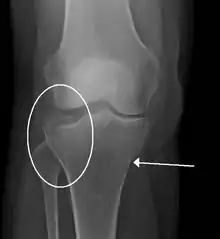

Lipohemarthrosis (presence of fat and blood from bone marrow in the joint space after an intraarticular fracture) seen on X-ray in a person with a subtle tibial plateau fracture Lipohemarthrosis (presence of fat and blood from bone marrow in the joint space after an intraarticular fracture) seen on X-ray in a person with a subtle tibial plateau fracture

Subtle tibial plateau fracture on an AP X ray of the knee Subtle tibial plateau fracture on an AP X ray of the knee

A tibial plateau fracture seen on X-ray A tibial plateau fracture seen on X-ray